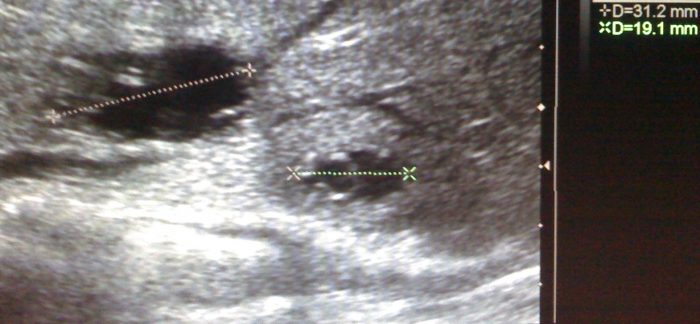

Эхинококк молочной железы.

Заболевание вызывается Echinicoccus granulosus в личиночной стадии развития паразита. Заражение происходит традиционным для эхинококкоза путем — через пищеварительный тракт. В молочную железу возбудитель попадает гематогенно, пройдя на своём пути два физиологических барьера — печень и легкие. Последнее обстоятельство определяет не только низкую частоту эхинококкоза молочной железы, но и редкость изолированных ее поражений. Частота поражения молочной железы эхинококком не более 0,05% от всех локализаций заболевания. Среди заболеваний молочной железы эхинококк описывается как казуистика.

Эхинококковый пузырь в молочной железе имеет типичное для этого патологического процесса строение с трехслойной стенкой состоящей из соединительнотканной капсулы, хитиновой оболочки и герминативного слоя. При длительном существовании заболевания, что возможно, когда пациентки наблюдаются по поводу доброкачественных новообразований, существенный вклад в особенности хирургической тактики и прогноз вносят фиброзные изменения наружной (соединительнотканной) оболочки.

Клиника и диагностика. Эхинококк молочной железы не имеет характерных симптомов и редко диагностируется до оперативного вмешательства. Как правило, пациентки с эхинококком молочной железы в течение длительного времени находятся под наблюдением по поводу доброкачественного новообразования молочной железы. При осмотре в молочной железе определяется выпячивание, которое при пальпации имеет округлую форму и легко смещается в стороны, безболезненно, с кожей не спаянно, упруго- эластичной консистенции. Признаки воспаления появляются лишь при вторичном инфицировании. Оболочки паразита хорошо визуализируются при маммографии. Лабораторные исследования обнаруживают эозинофилию, положительна кожная реакция Кациони и серологические реакции (РСК, РИГА, реакция латекс- агглютинации).

1. УЗИ позволяет выявить кисты в органах брюшной полости.